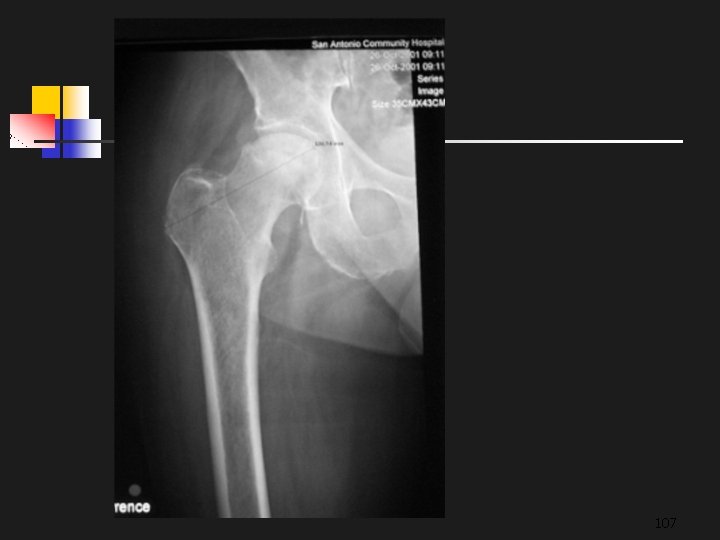

To Produce Quality Images For Conventional Projection or CR Radiography: The same rules, theories, and laws still apply and can not be overlooked FFD/OFD (SID/SOD) Inverse Square Law Beam Alignment Tube-Part-Film Alignment Collimation Grids Exposure Factors: KVP, Ma. S Patient Positioning 106

107